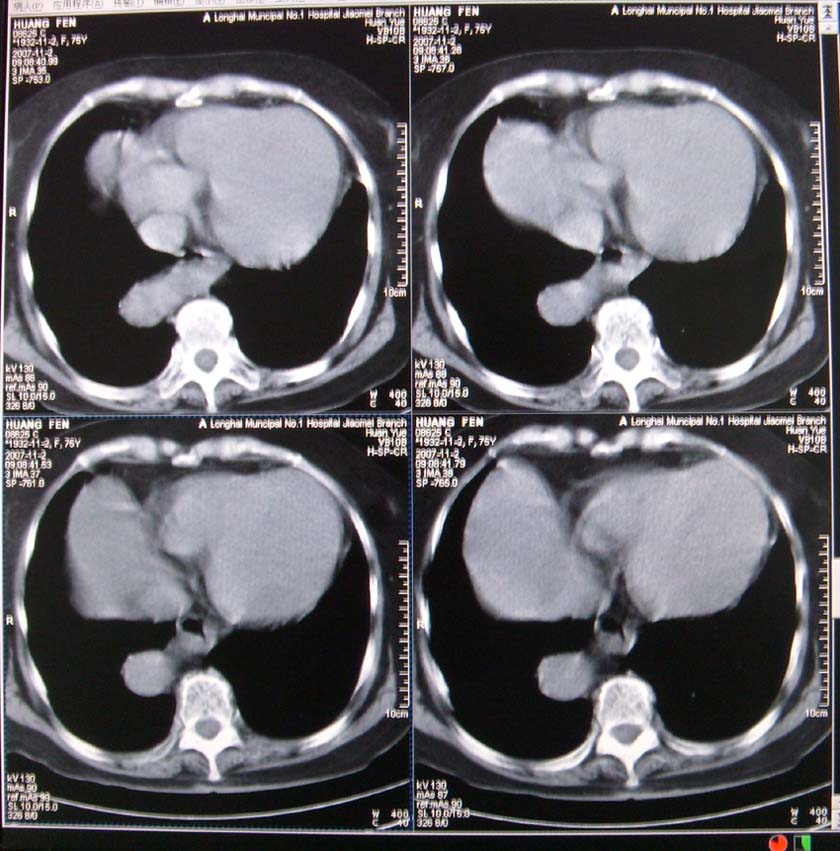

以下是引用xiaoniu在2007-11-4 12:05:00的发言:[br]这是胸主动脉迂曲延长造成的下段向右移行的影像表现,应该是:胸主动脉移行段。[br]

以下是引用nanjing在2007-11-4 12:21:00的发言:[br]降主动脉迂曲移位。